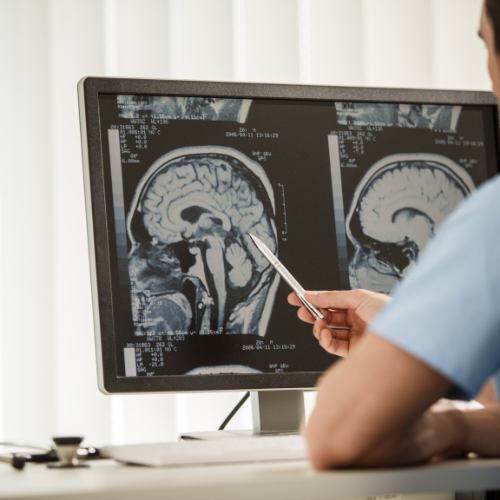

Beyin Tümörleri Beyin tümörlerinin nedenleri çok iyi bilinmemektedir ama radyasyon, genetik hastalıklar,aile bireylerinde tümör olması, bağışıklık sistemini etkileyen hastalıklar, stress ve çeşitli çevresel kanserojen maddelere maruz kalmak risk faktörü olarak kabul edilmektedir. Beyin tümörlerinin hücrelerin kromozom yapılarında yer alan belirli genlerin hasarlanması veya uygun fonksiyon görmemesi sonucu oluştuğu düşünülmektedir. Genlerdeki bu hasarlanma veya fonksiyon bozukluğu […]

Hipofiz tümörü, hipofiz bezi (beyinde yer alan endokrin bez) hücrelerinde anormal büyüme veya çoğalma sonucunda oluşan bir tümördür. Tümörün tipine, büyüklüğüne ve yerine bağlı olarak çeşitli semptomlar ortaya çıkabilir. Hipofiz tümörleri, iki gruba ayrılır: Fonksiyonel ve nonfonksiyonel tümörler. Fonksiyonel tümörler, hipofiz tarafından salgılanan hormonları etkileyerek hormonal değişikliklere neden olurken, nonfonksiyonel tümörler hormon salgılamaz. Hipofiz tümörünün […]